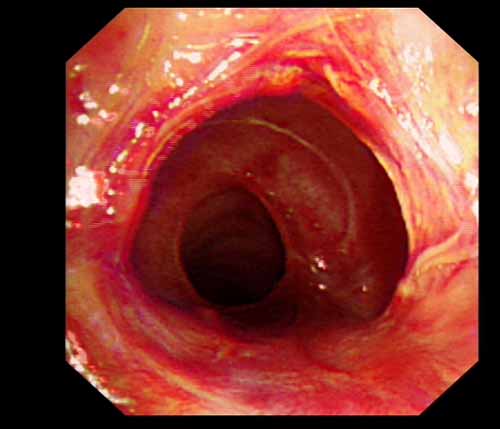

患者李某某,女,45歲,因氣管插管咳嗽、喘憋10天入院。頸部CT檢查示聲門下約20mm處氣管明顯狹窄,狹窄段長約26mm,最窄處直徑約4.4mm。支氣管鏡檢查見聲門下約2cm氣管呈漏斗狀縮窄,直徑約4-5mm,支氣管鏡無法通過。經(jīng)科室討論,決定行電子支氣管鏡下氣管球囊擴張治療。與患者及家屬充分溝通并經(jīng)三方見證談話簽署知情同意書后,在患者持續(xù)吸氧、局麻下,科主任于世倫主任醫(yī)師帶領(lǐng)治療小組為患者實行電子支氣管鏡下氣管球囊擴張術(shù)。手術(shù)過程順利,出血量很少,術(shù)后患者呼吸困難癥狀即可明顯緩解。10天后行二次擴張,患者日?;顒訜o明顯喘憋,二次術(shù)后5天出院。

術(shù)后擴張開的氣管管腔